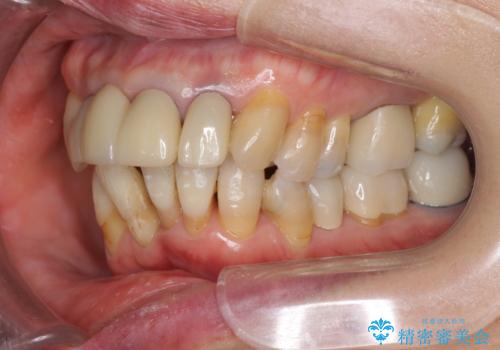

- 前歯の見た目・歯並び・銀歯の見た目の改善を求めて来院されました。

まずガタ付きの強い歯並びをマウスピース矯正インビザラインで整えたのち、セラミック治療による審美性の改善を計画します。